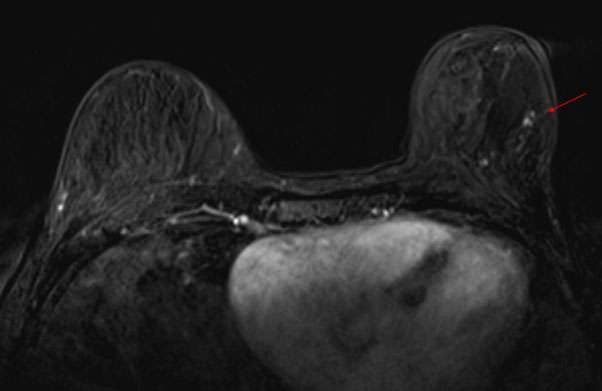

Case: Paget's Disease Figure 1

Figure 1: CC and MLO mammograms of the left breast. There is subtle skin thickening of the nipple and areola. An overlying sticker has been placed to denote the area of skin changes as indicated by the patient.